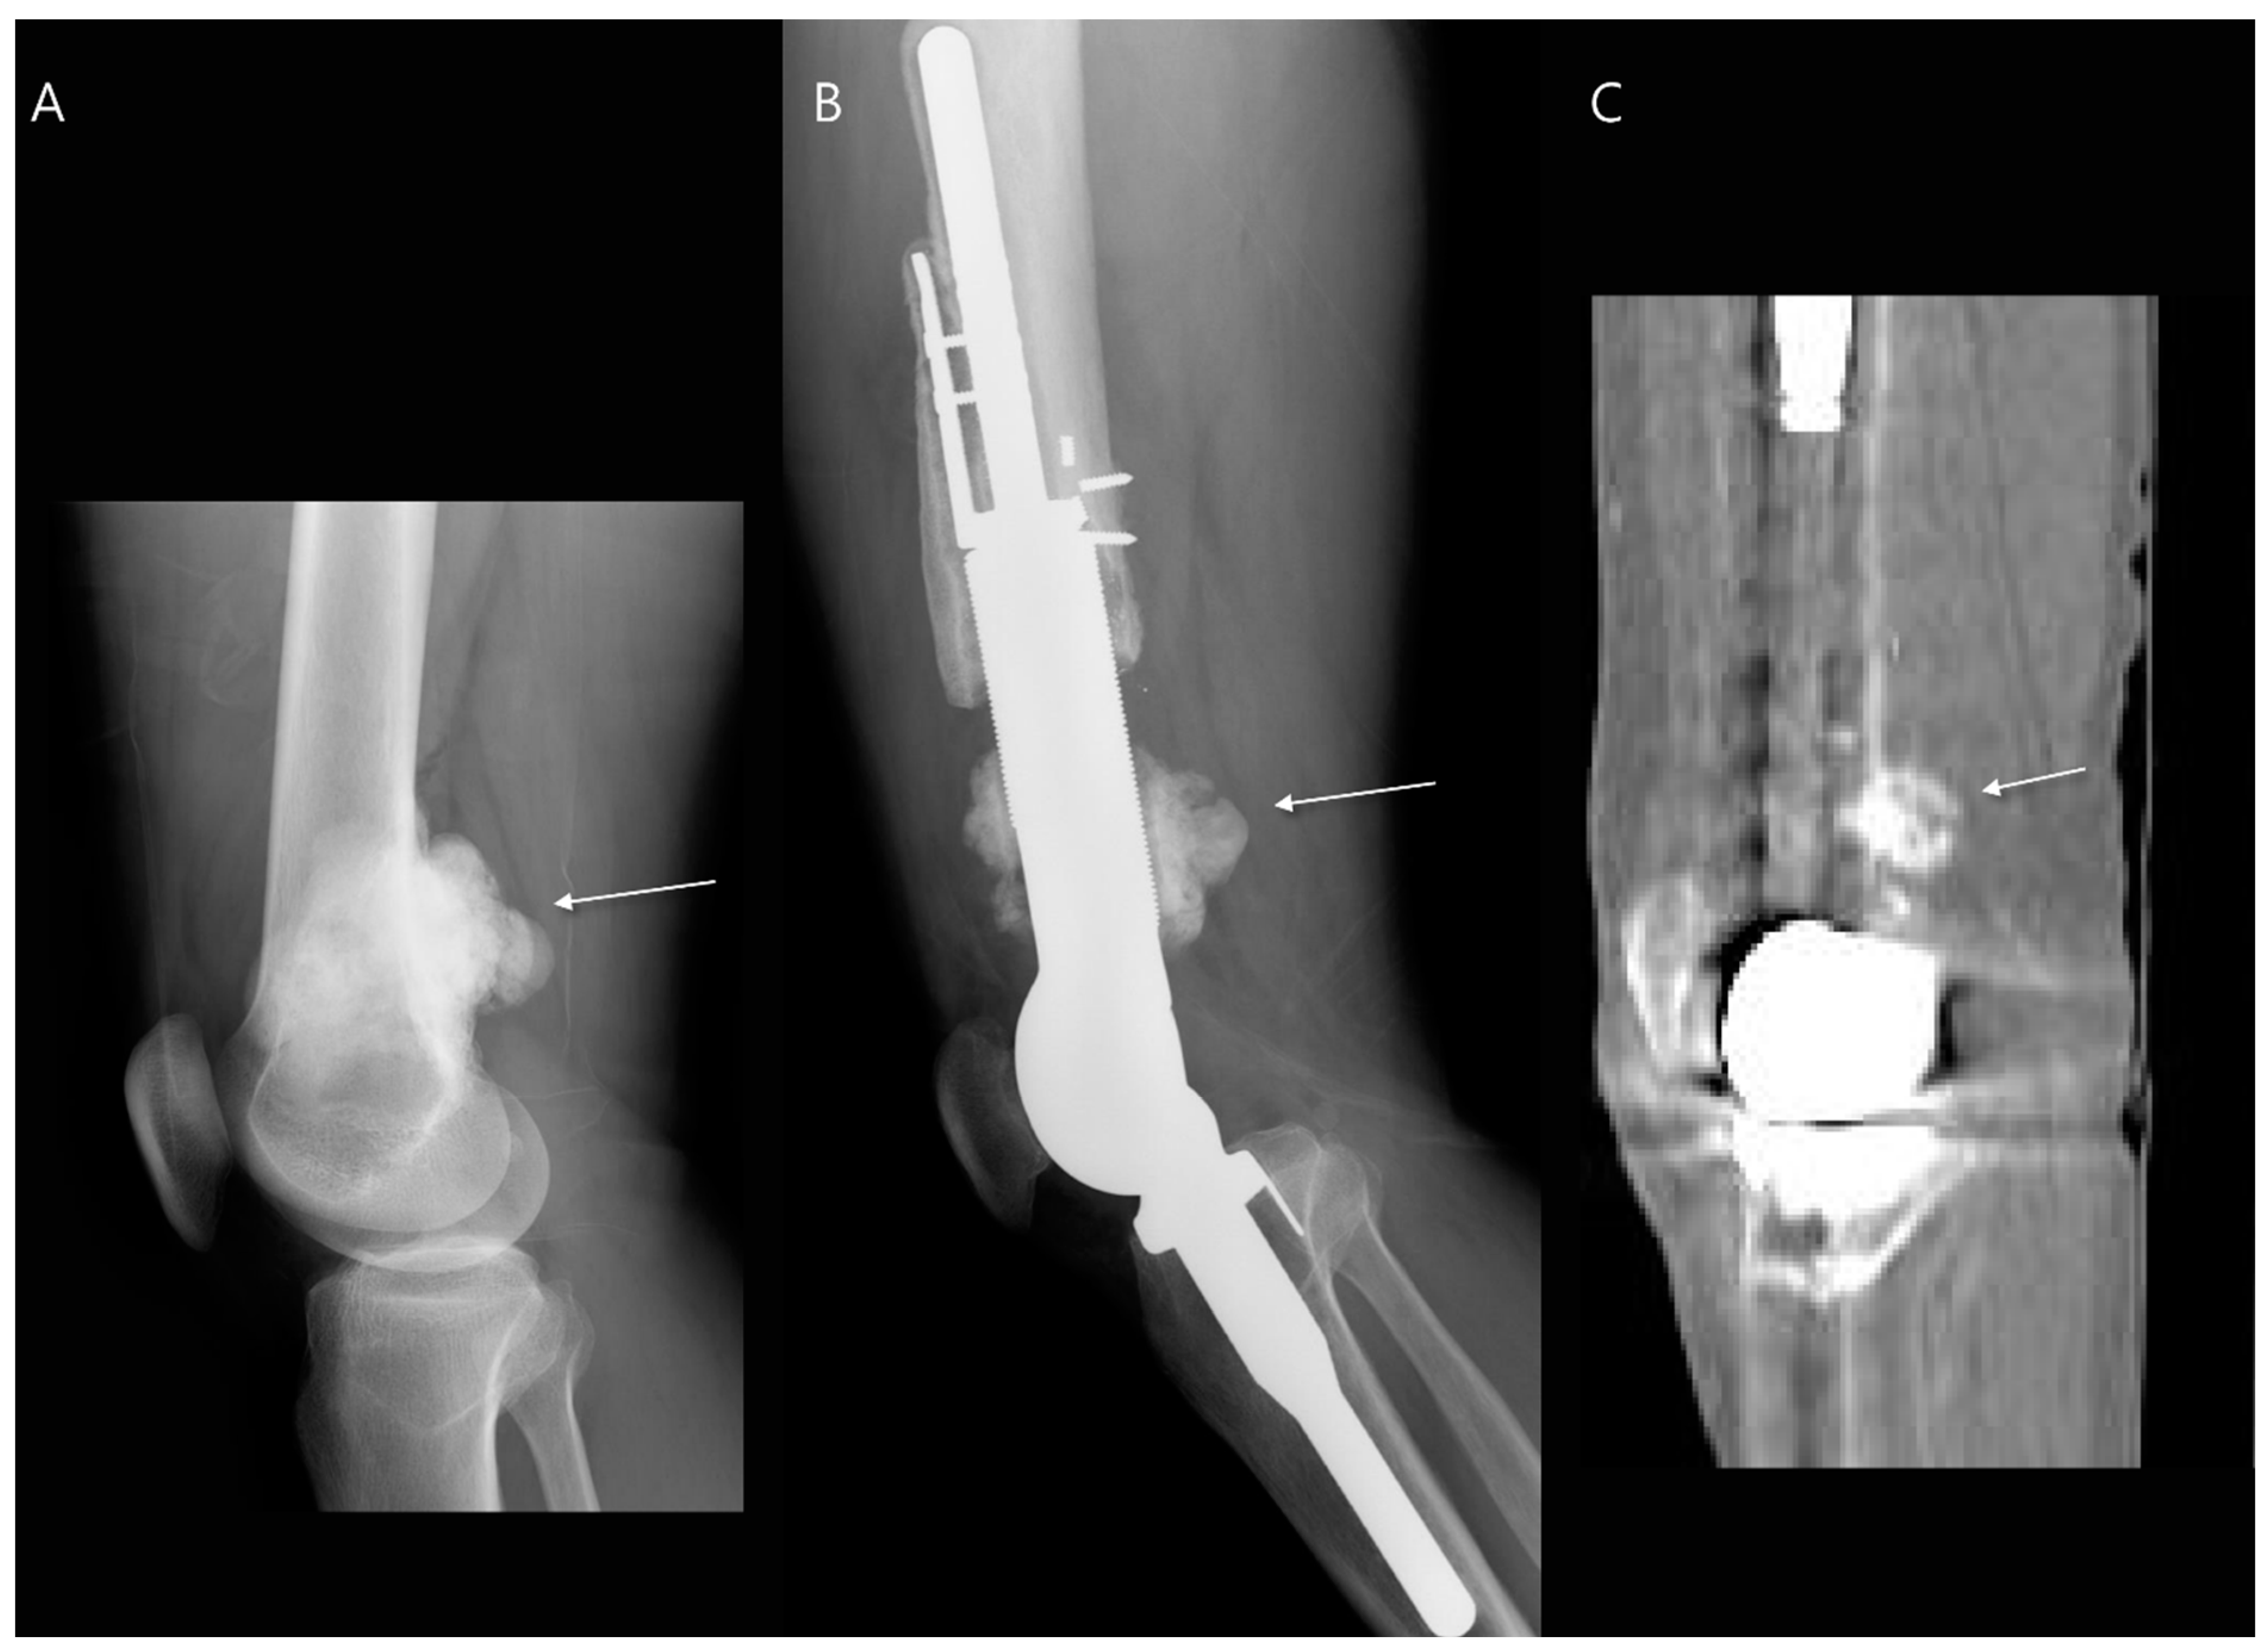

- Turcotte, R.E.; Stavropoulos, N.A.; Toreson, J.; Alsultan, M. Radiographic assessment of distal femur cemented stems in tumor endoprostheses. Eur. J. Orthop. Surg. Traumatol. 2017, 27, 821–827. [Google Scholar] [CrossRef]

- Henderson, E.R.; Groundland, J.S.; Pala, E.; Dennis, J.A.; Wooten, R.; Cheong, D.; Windhager, R.; Kotz, R.I.; Mercuri, M.; Funovics, P.T.; et al. Failure mode classification for tumor endoprostheses: Retrospective review of five institutions and a literature review. J. Bone Jt. Surg. 2011, 93, 418–429. [Google Scholar] [CrossRef]

- Shah, A.; Cardoso, F.N.; Souza, F.; Montreuil, J.; Pretell-Mazzini, J.; Temple, H.T.; Hornicek, F.; Crawford, B.; Subhawong, T.K. Failure Modes in Orthopedic Oncologic Reconstructive Surgery: A Review of Imaging Findings and Failure Rates. Curr. Oncol. 2024, 31, 6245–6266. [Google Scholar] [CrossRef]